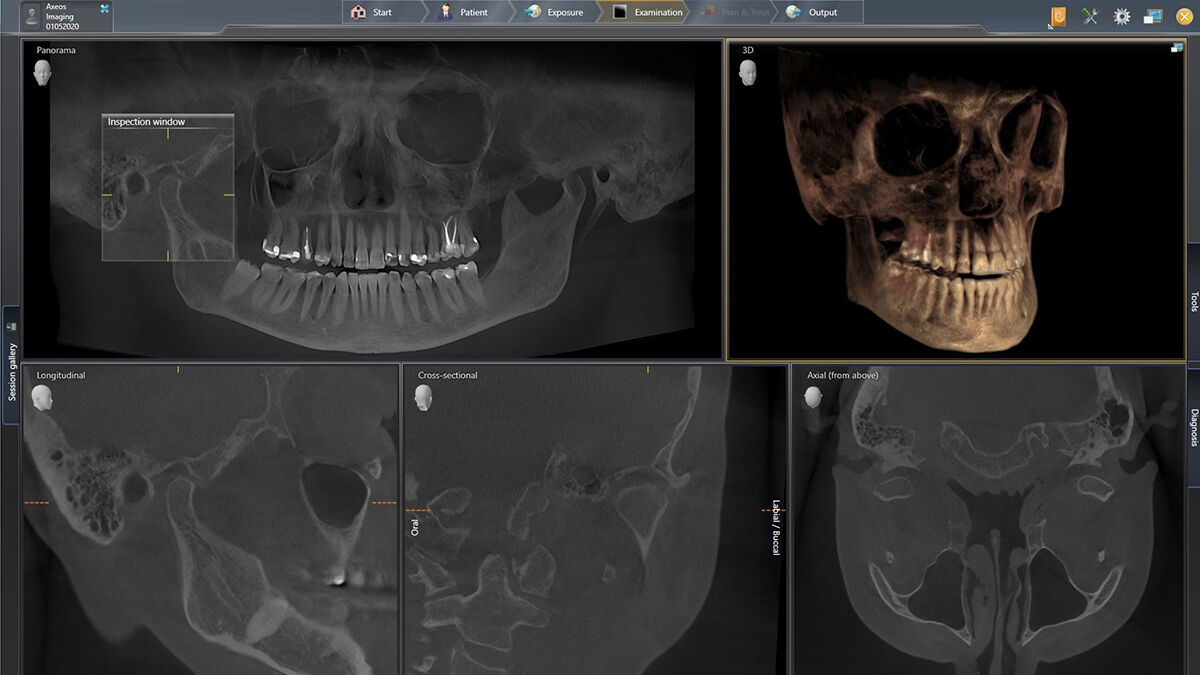

We developed a 10-point concept for easy patient positioning and X-ray imaging. Our concept is primarily about two things: high image quality and comfort for the patient and the assistant. This concept supports and provides the tools needed to ensure high-quality images for treatment analysis and focuses on ergonomics and comfort for the patient and assistant.